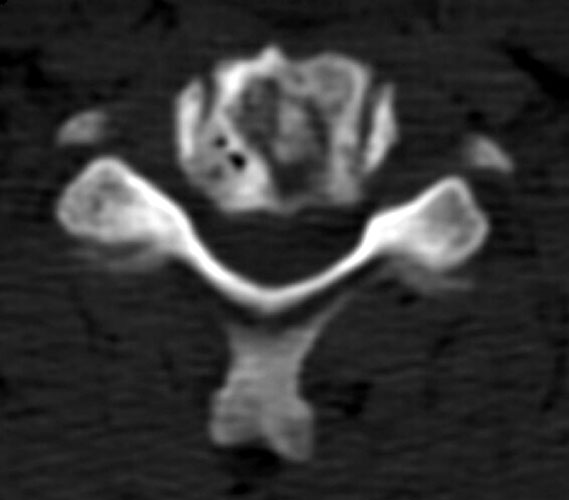

graft site worrisome for resorption. Figure _. Axial CT examination, without

The axial images, and the sagittal reconstructions (not

shown) show some central lucency in the region of graft placement,

suggesting partial resorption of the graft material. |